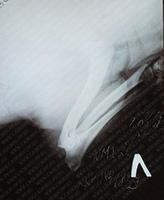

Снимок хвоста для себя, после предполагаемой травмы в игре с сестрой.

Без наркоза в возрасте 2-х месяцев.

Мнение врача: каких-либо травм и паталогий нет.